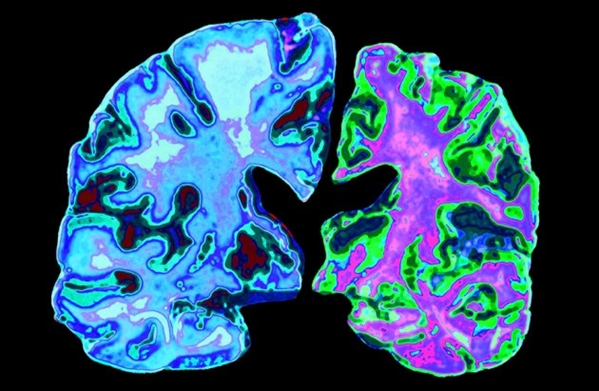

这个内部卫星导航系统的一个关键组成部分是大脑内嗅皮质,而这真是阿尔茨海默症患者首先受损的区域之一,也就可以解释为什么“迷路”是阿尔茨海默症的首发症状之一。然而,临床上用于诊断病情的认知测试无法测试“导航”是否有问题的。